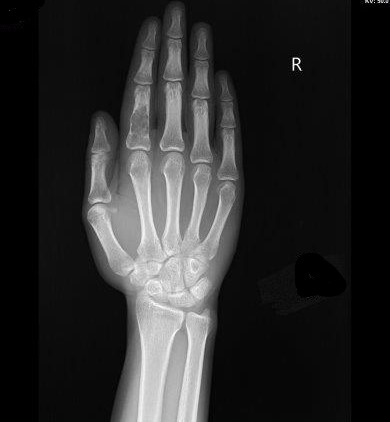

Welche Pathologie erkennen Sie am vorliegenden Röntgenbild?